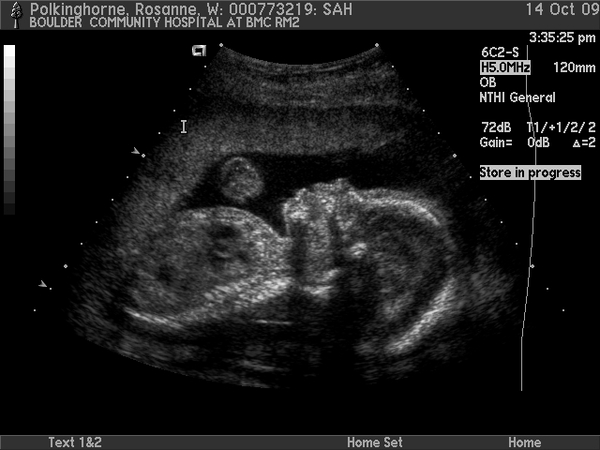

Sam in utero